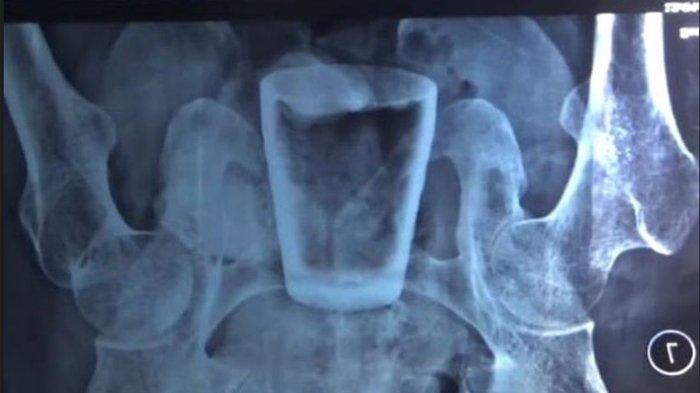

Sebuah gelas kaca ditemukan dalam perut pria tersebut.

Bukan dalam waktu singkat, gelas kaca yang pecah pada bagian atasnya itu sudah berada dalam perut pria tersebut selama 3 bulan.

Pihak rumah sakit kemudian melakukan pemeriksaan dengan rontgen.

Berdasarkan pemeriksaan medis, terdapat gelas di dalam perut Lasiadi.

“Kami foto rontgen dulu, ternyata ditemukan bentukan berupa gelas,” kata Humas RDS Balung Doddy Radhi Sakti yang dihubungi Kompas.com via telepon seperti dikutip dari pemberitaannya, Rabu (6/4/2022).